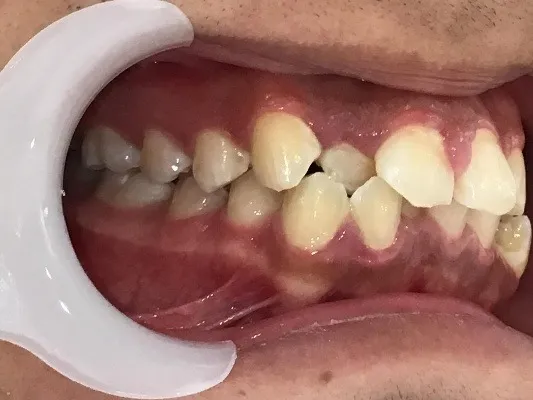

今回は他院さんでインビザライン矯正治療を受けていた患者様を引き継いで当院でインビザライン治療を継続した症例をご紹介致します。

今回はマウスピース矯正を主軸にした矯正ですが、一部ワイヤー矯正も併用して改善しております。

マウスピース矯正のみしか行っていない歯科医院では対処しきれない場合もあり、ワイヤー矯正とマウスピース矯正どちらも行える歯科医院で矯正治療を始めることがきれいな歯並びに近づける方法です。